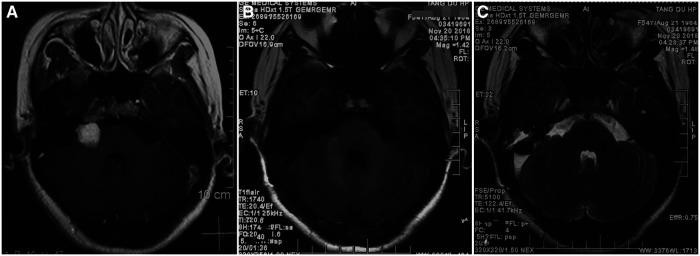

A 54-year-old woman who had undergone GKS 10 years previously for a right VS was admitted to our hospital in 2018 because of sudden onset of severe vertigo and vomiting, accompanied with unsteady gait. During tumor resection, a dissecting aneurysm arose from the main trunk of AICA was encountered accidently within the tumor. The aneurysm was successfully treated with direct clip ligation, sparing the parent vessel. Data about this case were combined with those of other 11 radiation-related AICA aneurysm cases retrieved from the current literature. The following parameters were evaluated: Age, Sex, Diagnostic method, Location of aneurysm, Age of radiotherapy (Years)/Latency, Rupture, x-ray dosage, Type of radiotherapy, History of surgical resection of VS, Aneurysm Type, Morphology, Number, Treatment, Operative complications, Sequela, Outcome. VS RRAs mainly occurred in women (75%) with a median age of 62.5 years and were mainly located on AICA. Ruptured aneurysms accounted for 75.0% of the total cases. This paper reported the first VS case admitted with acute AICA ischemic symptoms. Cases with sacciform-like, irregular and fusiform-shaped aneurysms accounted for 50.0%, 25.0% and 25.0% of the total, respectively. After surgical treatment, 75.0% patients recovered, except for 3 patients who developed new ischemic consequence.